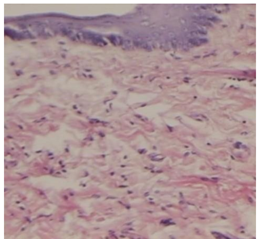

正常口腔黏膜组织 溃疡黏膜组织